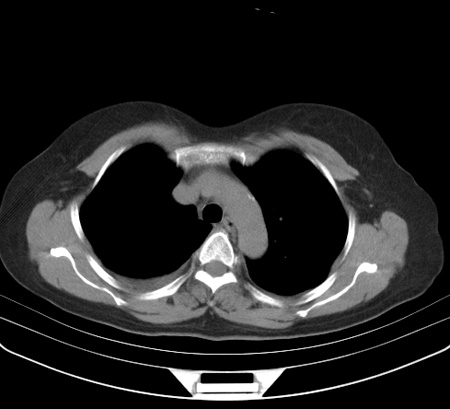

以下是引用余辉在2009-2-19 20:10:00的发言:[br]多考虑急性感染性病变,右中叶尚可见多枚小斑片状影,多为化脓性肺炎,双侧胸腔积液

以下是引用随光逐影在2009-2-19 20:33:00的发言:[br]1)考虑右肺炎症;建议抗炎治疗后复查。2)双侧胸腔积液(以右侧为甚)。

以下是引用花凤凰在2009-2-19 20:46:00的发言:[br]病人有发热,胸痛急性起病,主要病变位于右肺中叶外侧段,呈楔行改变,位于外带胸膜下,考虑为肺梗塞可能!!!!!!!!!!!!!!!!!!!!!!!!!!!!!!!!!!!